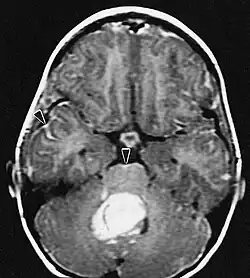

Medulloblastoom

Het medulloblastoom is een zeer kwaadaardige tumor van het centrale zenuwstelsel. Deze wordt gevormd uit zeer primitieve zenuwcellen en bevindt zich altijd in het gebied van de kleine hersenen, zit in de buurt van de hersenstam medulla oblongata. De tumor zaait dikwijls uit binnen het centrale zenuwstelsel. De prognose hangt af van veel factoren. Jonge kinderen en patiƫnten met uitzaaiingen hebben een slechte prognose. De behandeling hangt af van de leeftijd en de uitbreiding van de ziekte. Patiƫnten met een leeftijd boven de 5 jaar, die geen uitzaaiingen hebben en waarbij de tumor geheel of vrijwel geheel operatief verwijderd is worden behandeld volgens een protocol van de SIOP. Er wordt gestart met bestraling van het gehele centrale zenuwstelsel en aansluitend wordt gedurende ongeveer een jaar chemotherapie gegeven. In deze gevallen is de kans op overleving ongeveer 75 %.